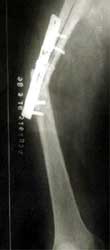

股骨远段骨折,4次钢板固定均失败,改用带锁髓内钉固定,7个月后骨折愈合。